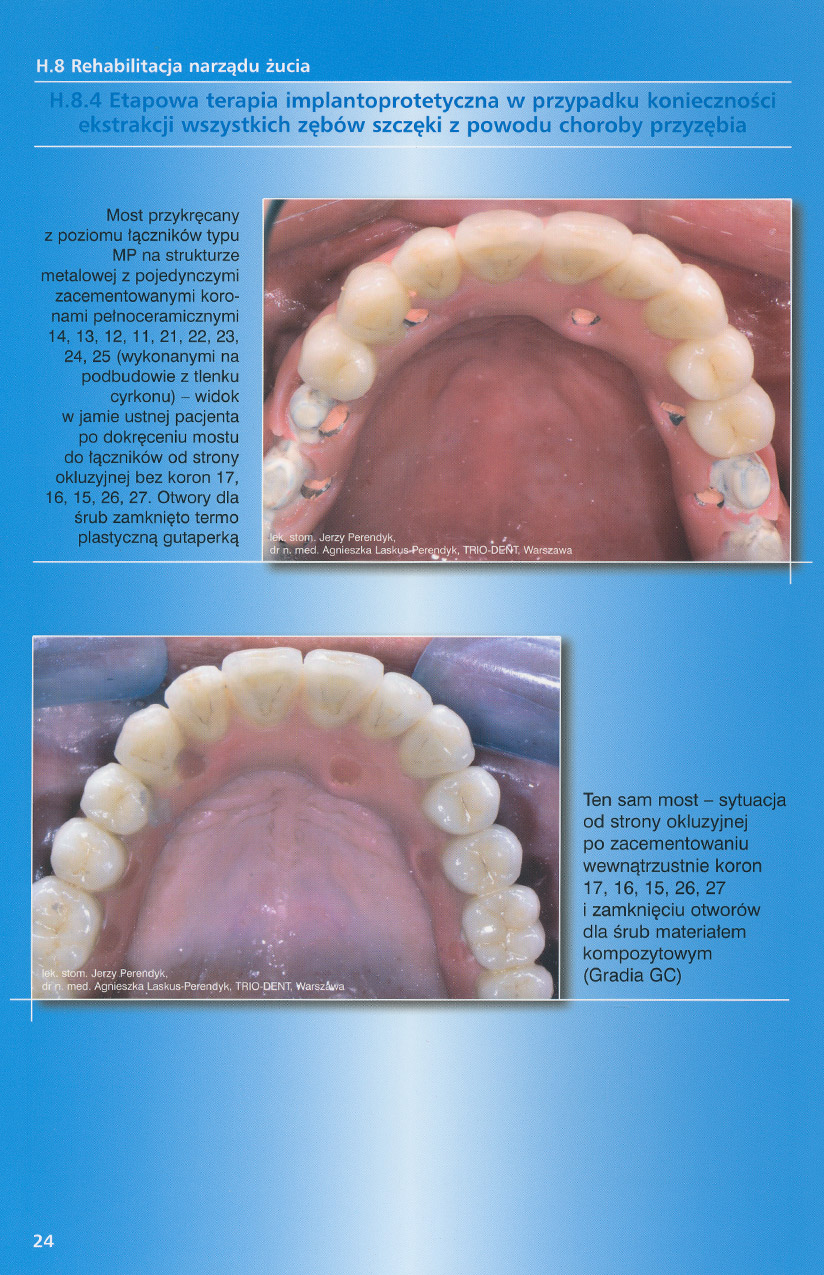

zobacz więcejGaleria przypadków klinicznych, obrazująca proces terapeutyczny od stanu wyjściowego aż do oddania ostatecznej pracy uzupełnienia brakującego uzębienia.